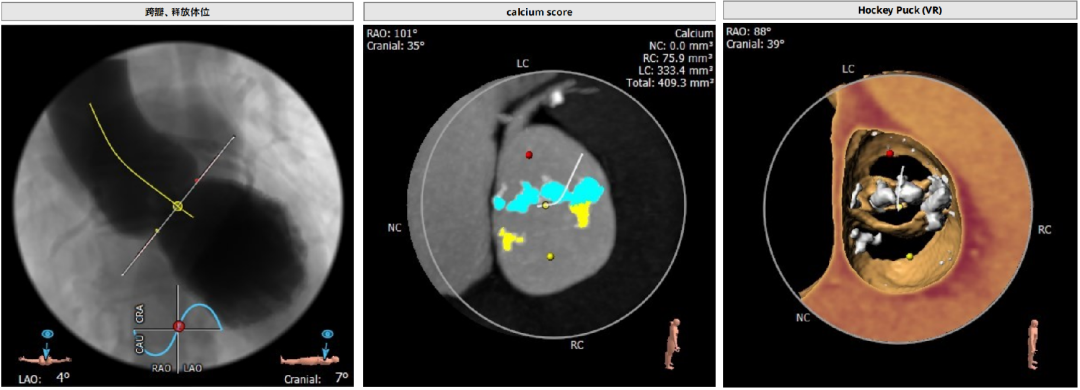

CT分析

Anulus 27,LVOT 34.2,短径25.9,STJ高度可,初步预估32/29瓣膜。

窦部短径26mm、左右冠空间足够,冠脉高度可心脏角度51°、升主未增宽。

体位:LAO 4° CRA 7° ;type0型二叶瓣一个角度即可,有需要可测cusp-overlap角度;轻度钙化,位于瓣叶游离缘,基本不影响瓣膜位置。

心尖薄,导丝塑性需注意形态,入路可,右股做为主入路。

预装32瓣膜,25球囊扩